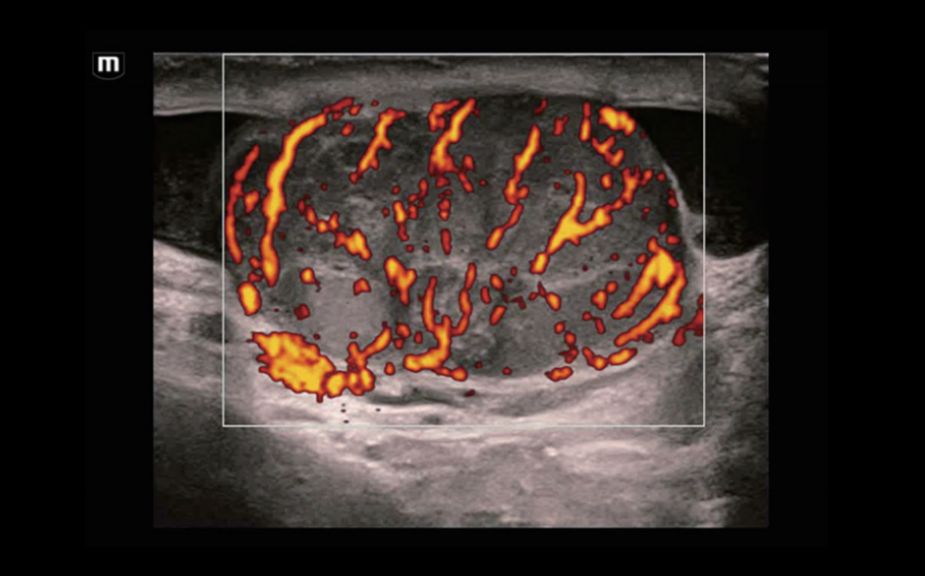

A Novel Approach of Vascular Hemodynamics: V Flow

Kolorowe wektory wskazuj? szybko?? i kierunek przep?ywu kom├│rek krwi. Dzi?ki wysokiej cz?stotliwo?ci od?wie?ania obrazu, V Flow zapewnia niezwykle ?yw?, dok?adn? i niezale?n? od k?ta nachylenia bramki dopplerowskiej wizualizacj? z?o?onych przep?yw├│w hemodynamicznych w naczyniach.

V Flow

A Novel Approach of Vascular Hemodynamics: V Flow

Kolorowe wektory wskazuj? szybko?? i kierunek przep?ywu kom├│rek krwi. Dzi?ki wysokiej cz?stotliwo?ci od?wie?ania obrazu, V Flow zapewnia niezwykle ?yw?, dok?adn? i niezale?n? od k?ta nachylenia bramki dopplerowskiej wizualizacj? z?o?onych przep?yw├│w hemodynamicznych w naczyniach.

V Flow